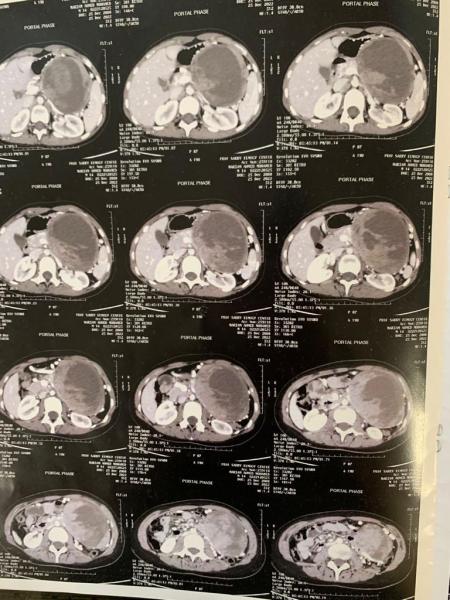

وبالنسبة للطفلة فكانت تعانى من بعض الامتلاء بمنطقة البطن بدون أى أعراض أخرى تذكر وقد تم تشخيصها عدة مرات بأنها تعانى من التهابات بالمعدة والقولون، وتلقت العلاج بدون نتيجة، وبدون تحسن ملحوظ، وقد تم مناظرتها بالعيادة الخارجية بمركز الجهاز الهضمى، وأوصى لها بعمل أشعة مقطعية ثلاثية الأبعاد متعددة المراحل ووجد أنها تعانى من ورم كبير بمنطقة البنكرياس، وحيث إن هذه الأورام نادرة الحدوث وسريعة الانتشار، فقد تم استكمال الفحوصات والتحاليل داخل المركز، وتم تحضيرها بشكل عاجل لاجراء الجراحة وتلقت اللقاحات اللازمة ما قبل الإجراءات.

وتشكل فريق للجراحة برئاسة الدكتور أمجد فؤاد رئيس أقسام الجراحة بكلية الطب، والدكتور أحمد حسين ، والدكتور عمر حشيش ، والدكتور محمد امجد ، وفريق تخدير برئاسة الدكتور امجد زغلول والدكتور حاتم صابر وأثناء الجراحة وجد أن الورم 20×24×31 سم وأنه موجود بمنطقة جسم البنكرياس بالكامل وأحاط بشكل كامل بالأوردة والشرايين الخاصة بالطحال وخلف المعدة زفى جراحة دقيقة ومعقدة استمرت أكثر من خمس ساعات متواصلة تم استئصال الورم بالكامل بشكل آمن وتم نقل الطفلة الى العناية المركزة لاستكمال العلاج .